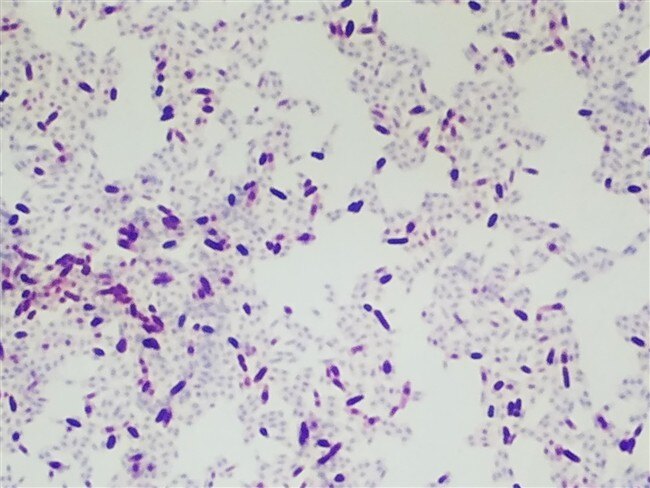

Acid Fast stains are used for identifying acid fast organisms. These bacteria will be stained red by the protocol.

Acid-fast organisms are stained red, while non-acid-fast organisms and the background are stained green or blue.  A major characteristic of mycobacteria is that they are “acid-fast” and once stained with aniline dye, basic fuchsin, they are difficult to decolorize, thus retaining the red color even when exposed to an acid alcohol rinse.